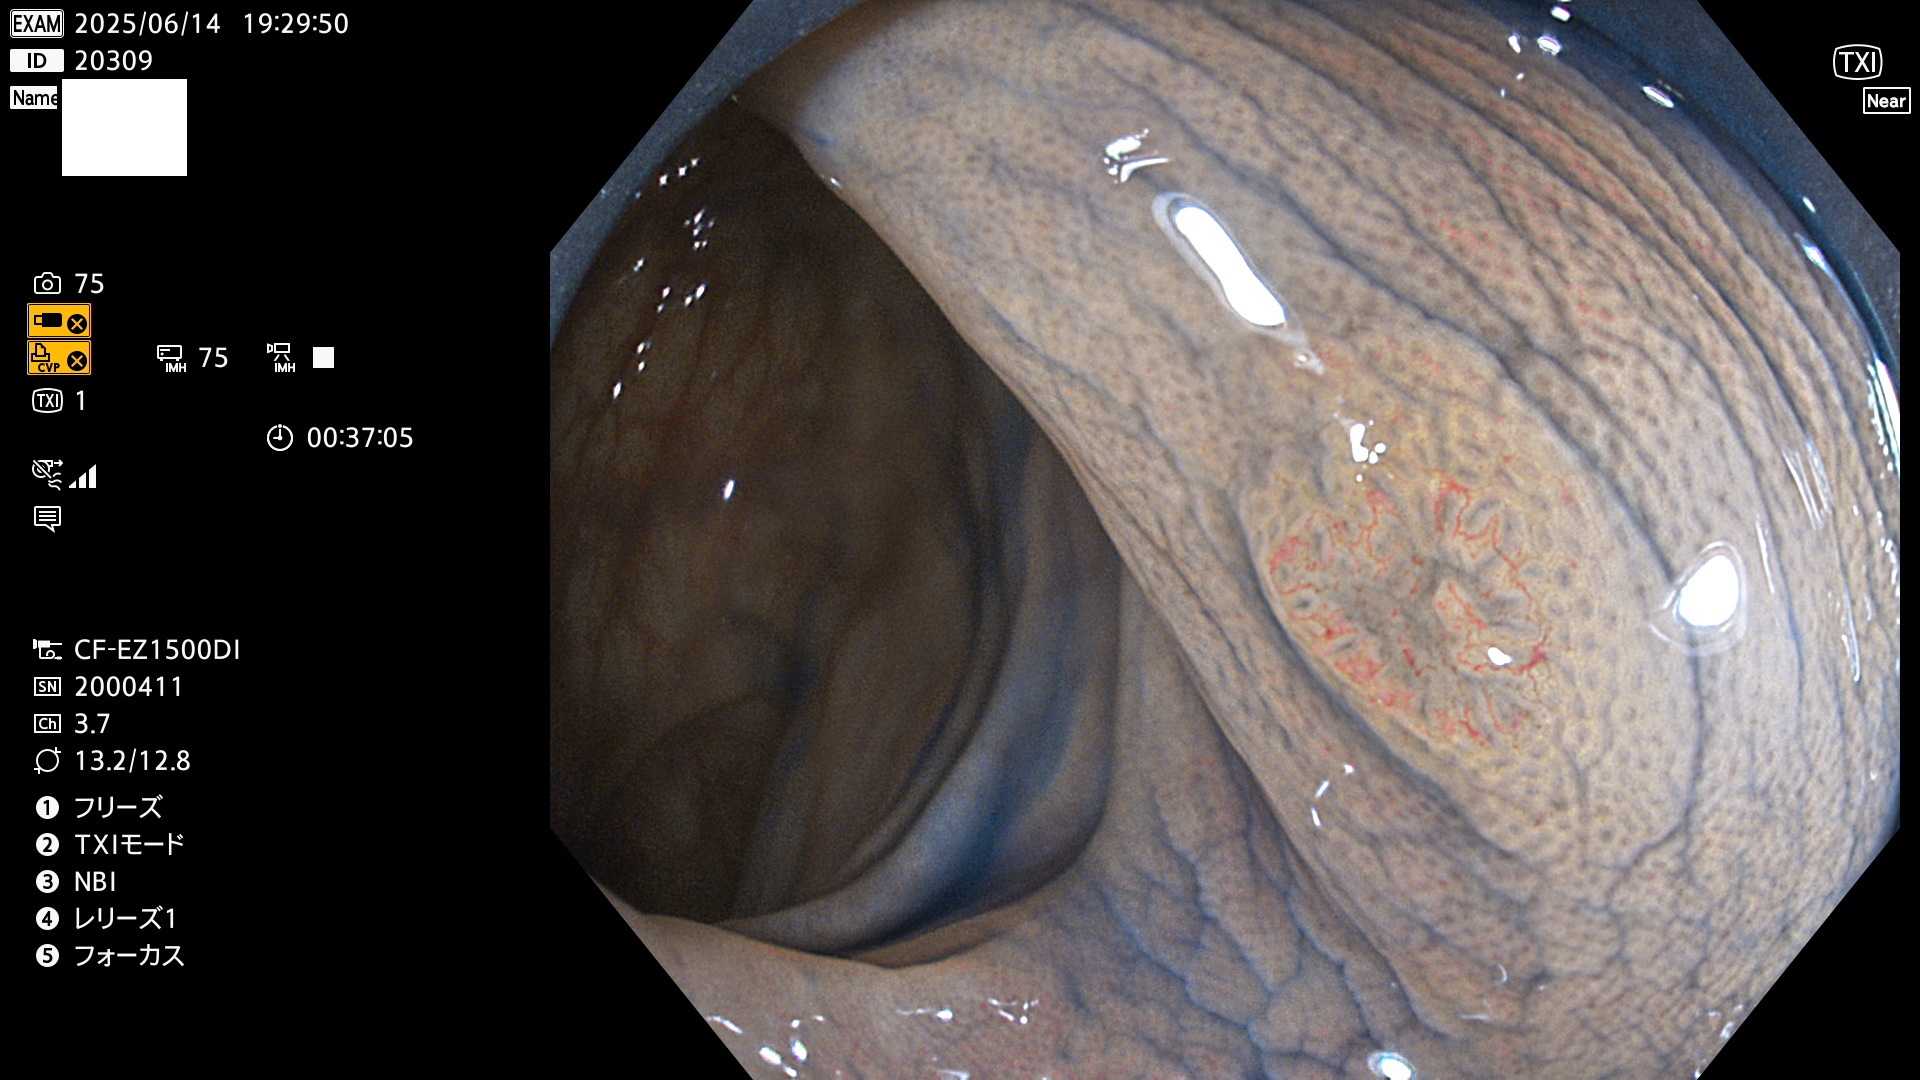

完全に平坦な物をUb、陥凹している物をUcと呼びます。Ubは認識が困難で、Ucはびらん(炎症)と紛らわしいために見落とされやすく、「内視鏡後・大腸癌」の原因になります。

抽出の対象期間 2025年6月12日〜6月15日の4日間(48件の検査)14個 (14/48=29%)